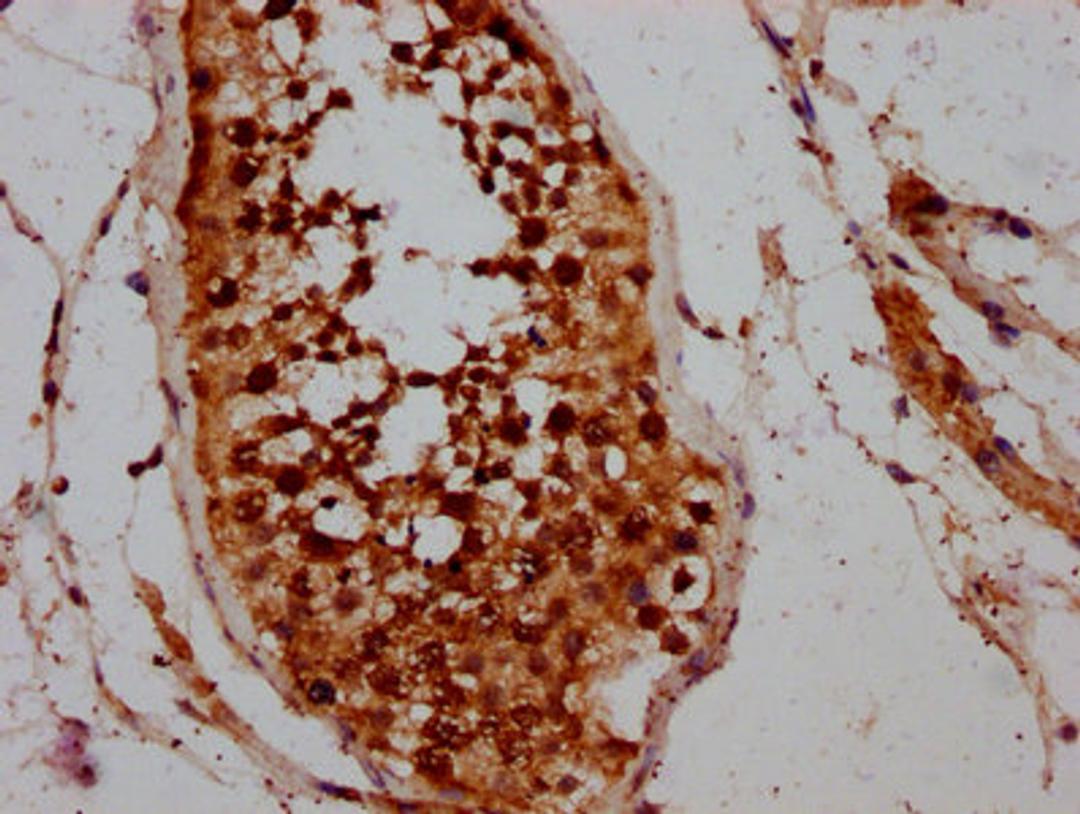

IHC image of CSB-PA004770LA01HU diluted at 1:200 and staining in paraffin-embedded human testis tissue performed on a Leica BondTM system. After dewaxing and hydration, antigen retrieval was mediated by high pressure in a citrate buffer (pH 6.0). Section was blocked with 10% normal goat serum 30min at RT. Then primary antibody (1% BSA) was incubated at 4°C overnight. The primary is detected by a biotinylated secondary antibody and visualized using an HRP conjugated SP system.